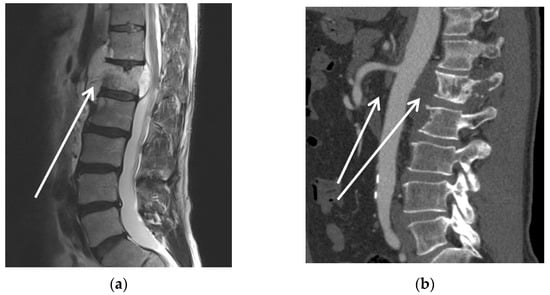

| 3 | m | 56 | Chordoma L1 | Spinal compression with impending paraplegia | Yes, proton therapy (50 Gy) | No | 1 | I |

| 4 | m | 41 | Retro-peritoneal rhabdoid sarcoma | hydronephrosis; patient’s wish for curative resection | Yes, proton therapy (50 Gy) | Yes | 0 | II |